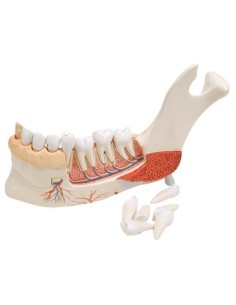

Erler Zimmer, modello anatomico di metà mandibola superiore e inferiore, ingrandita...

Erler Zimmer, modello anatomico per spiegare la corretta igiene orale D216